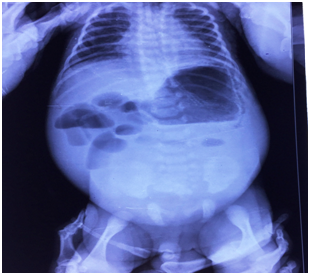

A 7‒day‒old baby boy delivered normally to a 29‒year‒old multipara female, was admitted with the complaints of non passage of meconium since birth, increasing abdominal distension for 4 days and a history of bilious vomiting at birth. At presentation the child’s general condition was poor. He was dehydrated with a heart rate=130/min and a delayed capillary refill time. His abdomen was grossly distended with overlying shiny skin and prominent visible veins. On rectal stimulation by an infant feeding tube, meconium staining was noted. An erect X‒ Ray of the abdomen showed multiple air‒fluid levels (Figure 1). The child received supportive care, oxygen by hood, intravenous fluids and antibiotics. Naso‒gastric (NG) tube decompression yielded bilious aspirate. On urinary catherization, 430ml of clear urine was aspirated at a single time. Child was stabilized and taken up for exploration in view of neonatal intestinal obstruction.

Figure 1 X‒ray abdomen erect of a 7 day baby boy showing multiple dilated loops with air‒fluid levels suggestive of intestinal obstruction.